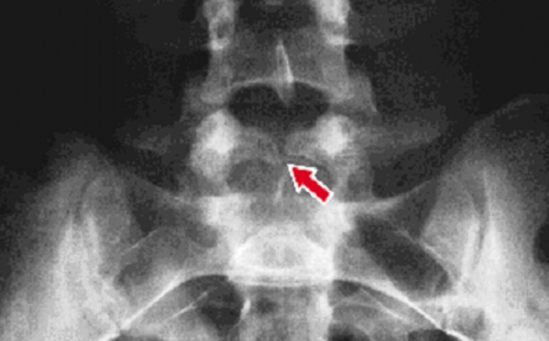

Old  Default Bài thuốc chữa gai đôi cột sống cực kỳ hiệu quả

Gai đôi cột sống là căn bệnh mang đến những cơn đau đớn cho người bệnh.Đặc biệt mỗi khi trái gió trở trời bệnh lại càng đau nặng hơn.Bài thuốc dưới đây sẽ giúp trị dứt điểm được các cơn đau của bệnh.